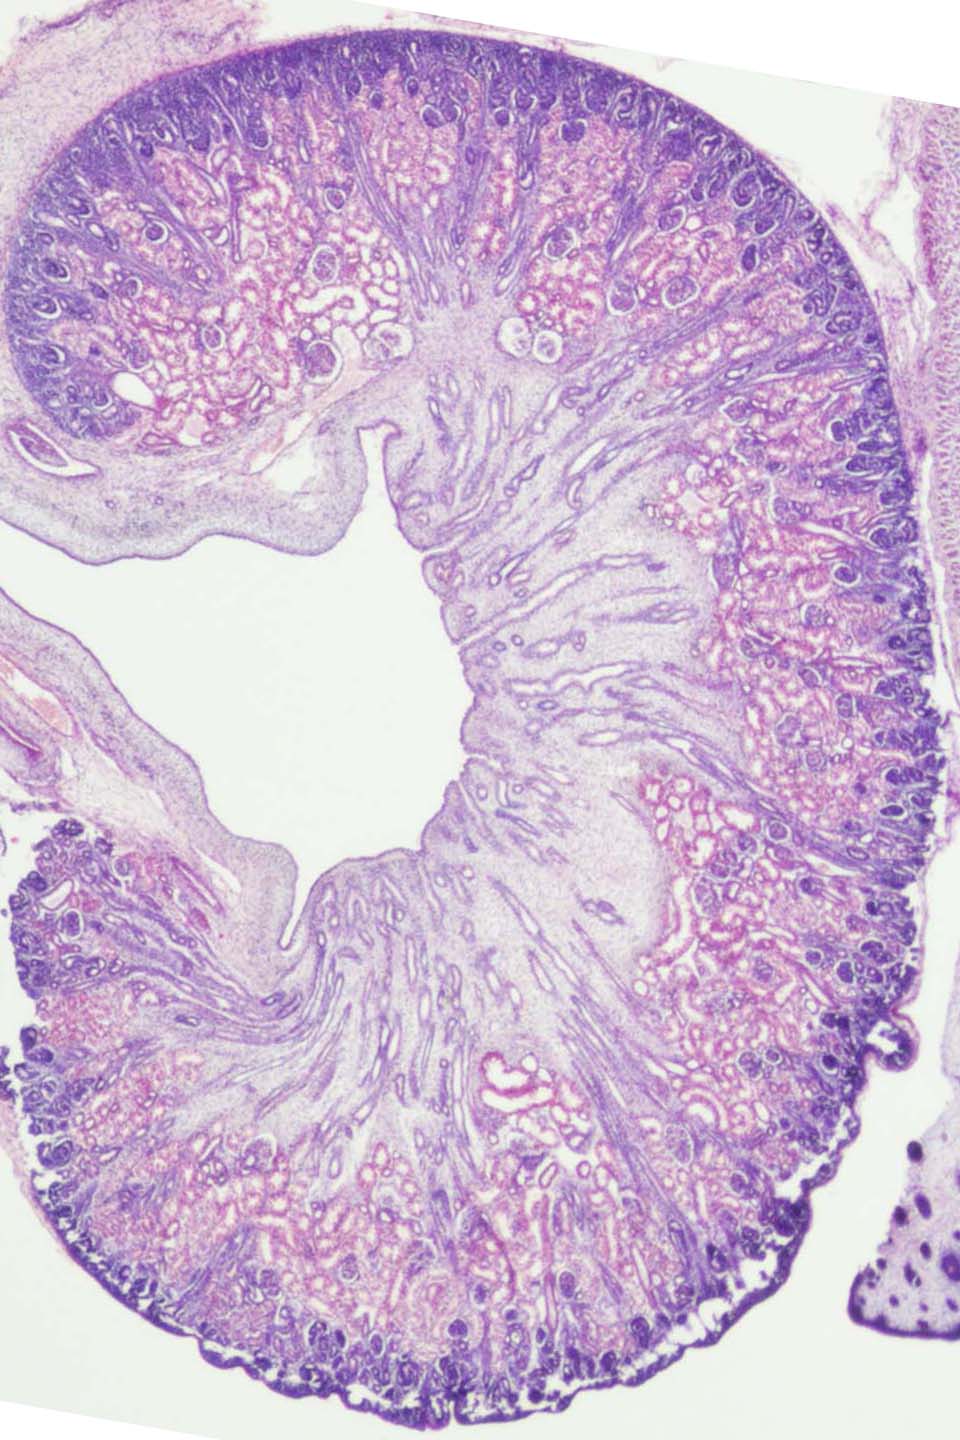

Kidney

Stage:

CfS > 23

Day:

d43